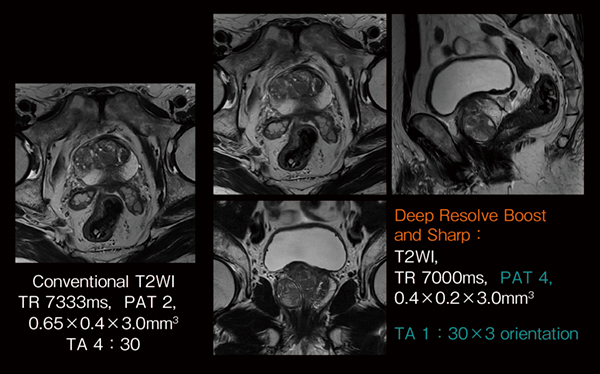

Siemens Healthineersでは,シーケンスごとに適したDeep Resolveのアルゴリズム開発を進めており,まず臨床において最も使用頻度が高いturbo spin echo(TSE)への適用を行い,撮像時間の短縮や高精細画像の取得を実現している2)。例えば,前立腺の高分解能T2強調画像の撮像に適用した場合,従来横断像のみに4分30秒の時間を要していた撮像を,Deep Resolveにより1/3の時間に短縮できるため,同じ4分30秒の撮像時間の中で冠状断像と矢状断像を追加した3断面の撮像を完了できる(図2)。このように,Deep Resolveを活用することにより,従来と同じ検査時間の中でより診断価値の高い画像の取得が期待できる。

図2 前立腺T2WI conventional TSEとDeep Resolve TSEの比較

従来の1断面の撮像時間で3方向撮像が可能となる。